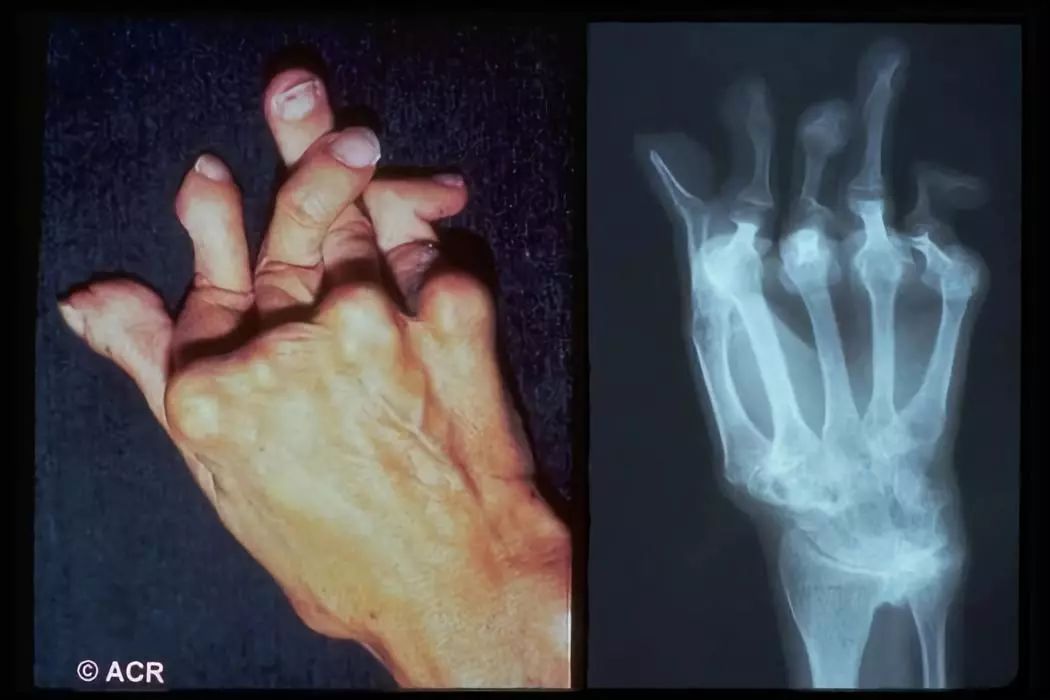

类风湿关节炎是什么?

类风湿关节炎(RA)是一种病因不明的,以侵犯关节滑膜为主要特征的慢性、炎症性、系统性结缔组织病,属于自身免疫性疾病。女性是类风湿性关节炎的重灾区,发病率为男性的23倍。可发生于任何年龄,高发年龄为4060岁。

表现为对称性、持续性关节红、肿、热、痛和功能障碍,主要侵及周围小关节和大关节,以近端指间关节、掌指关节和腕关节最常见,其它依次为足、肘、肩、踝、膝、颈、颞颌及髋关节等,后期可发展为关节畸形,乃至残废。